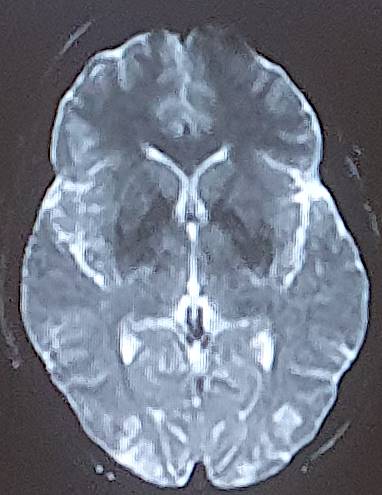

The average consultation time was 24.3 ± 14.4 hours, with extremes of 7 hours and 44 hours. Clinical presentations were headache (88.2%), visual disturbance (64.7%), disturbed consciousness (35.3%), epileptic seizures (23.5%) and motor deficit (29.4%) (Table 2). Mean systolic blood pressure was 190 ± 5.7 mmHg (extremes 150 - 24 mmHg), mean diastolic blood pressure 110 ± 5.1 mmHg (extremes 80 - 160 mmHg). Neuroradiological lesions (Figure 1) were edematous (88.2%), hemorrhagic (23.5%) and ischemic (11.7%). The topography of cerebral lesions was occipital (100%), parietal (82.3%), frontal (58.8%), temporal (47%), cerebellar (29.4%) and basal ganglia (23.5%) (Table 3).

Figure 1. Breakdown of cases by neuroradiological lesions.

Our findings on lesion topography (Figure 2 and Figure 3) are similar to those in the literature, which report that the parieto-occipital, frontal and temporal regions are most involved. More rarely, lesions may extend to the basal ganglia (14%), brain stem (13%) and splenium of the corpus callosum (10%) (Leroux et al., 2008). A normal CT scan does not exclude the diagnosis of PRES (Poma et al., 2014). Intracerebral hemorrhage is observed in 5% - 30% of PRES cases (Aracki-Trenkić et al., 2016; McKinney et al., 2012).

Figure 2. Bilateral occipital vasogenic edema.

Figure 3. Bilateral frontal-parietal-occipital edema with left lenticular hemorrhage.